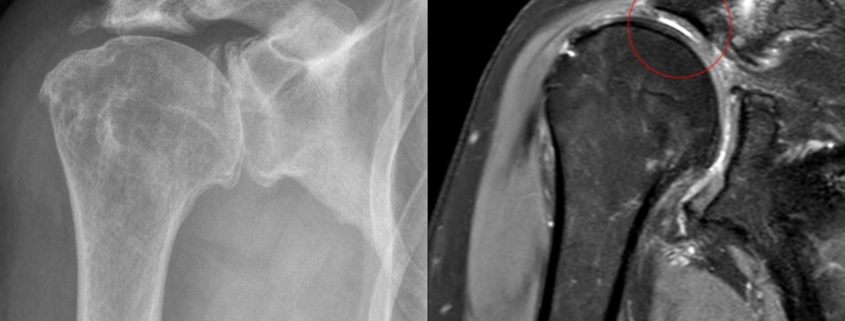

In early 2025, a landmark study published in JAMA Internal Medicine found something that's forcing doctors to rethink how they diagnose shoulder problems. Researchers scanned 602 adults aged 41 to 76 with MRI machines and discovered that 99% of them had at least one rotator cuff abnormality. Tears, tendon thickening, fraying—you name it, they had it.

But here's the kicker: 82% of these people had absolutely no shoulder symptoms. No pain. No weakness. No problems at all.

This finding upends everything we thought we knew about shoulder imaging. It reveals a massive gap between what an MRI shows and what actually matters clinically. And it's happening in clinics worldwide, leading to unnecessary treatments, escalating healthcare costs, and patient anxiety that could have been prevented.

When researchers looked more closely at specific types of abnormalities, something interesting happened. Full-thickness tears initially appeared more common in the symptomatic group. But when researchers adjusted their analysis for other confounding variables (like the presence of multiple additional abnormalities, age, body mass index), that difference essentially vanished.

In other words: even the most severe abnormality (full-thickness tear) didn't clearly correlate with whether someone had pain.